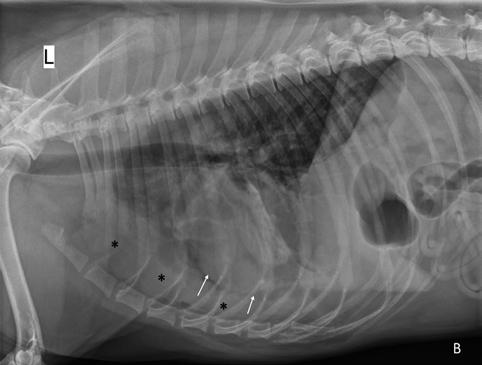

Se realiza la necropsia en la que se observa el corazón dentro del saco pericárdico con abundante líquido pericárdico. Se observa una gran masa redondeada de 7 x 5 x 3 cm en la base de la aorta, de consistencia firme, vascularizada, la cual al corte presenta vascularización y cavitaciones, áreas de hematoma y áreas de tejido graso y tejido fibroso. Se observa engrosamiento y degeneración de ambas válvulas atrioventriculares y, además, presencia de un nódulo en la válvula tricúspide de aspecto liso, color beige, no vascularizado de 1,5 cm. Se realizó en la toma y envío de muestras de las lesiones observadas en la base de corazón y tricúspide (Figs. 7, 8, 9 y 10). El análisis histopatológico de ambas lesiones confirma la sospecha diagnóstica de quemodectoma, siendo el nódulo tricúspide metástasis de la neoplasia principal en la base aórtica (Fig. 11), ya

Figura 7. Imagen de corazón evidenciando masa en base aórtica (flecha). Figura 8. Detalle de masa adherida a aorta. Masa esponjosa, cavitada, vascularizada, con áreas de necrosis y tejido adiposo. Figura 9. Detalle de masa tricúspide (flecha). Visión desde aurícula derecha. Figura 10. Detalle de masa tricúspide (flecha) adherida a las valvas. Vista gracias a la apertura completa del ventrículo derecho.

que al examen microscópico en ambas localizaciones se observaron células de bordes indefinidos, citoplasma escaso a moderado eosinófilo finamente granular, núcleo redondo, cromatina granular y nucléolo variablemente presente, pequeño, redondo y basófilo. También se observó anisocitosis y anisocariosis moderadas. Se reconocieron mitosis en 10 campos de 40X a través de la autólisis en la muestra. Se diagnosticó así en la muestra de aorta y tejido adiposo de la base cardíaca un carcinoma neuroendocrino, consistente con quemodectoma, con invasión intravascular. En la muestra de la válvula tricúspide y miocardio de la pared ventricular derecha se diagnosticó metástasis valvular miocárdica de carcinoma neuroendocrino y degeneración mixomatosa de la válvula tricúspide, marcada, crónica y difusa (endocardiosis). Además, la lesión neoplásica en tricúspide presentaba carácter infiltrativo hacia el tejido miocárdico de la pared ventricular derecha y epicardio (Fig. 12).